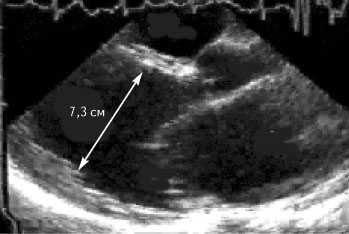

При поступлении в клинику состояние средней тяжести. Ортопноэ. Цианоз лица. Выраженные отеки ног. В легких выслушиваются незвонкие мелкопузырчатые хрипы в нижних отделах легких. Частота сердечных сокращений 92 в минуту. АД 110/70 мм рт. ст. Тоны сердца глухие, систолический шум на верхушке сердца. Живот увеличен в объеме за счет свободной жидкости. Размер печени по Курлову 10/4-10-8 см. Селезенка не увеличена. На ЭКГ блокада левой ножки пучка Гиса. При рентгенографии выявлено увеличение сердца в размерах, усиление легочного рисунка за счет застоя жидкости. При эхокардиографии обнаружены дилатация всех камер сердца (диастолический размер левого желудочка 7,3 см) и снижение фракции выброса левого желудочка до 23% (рис. 1). Уровень калия крови — 3,3 ммоль/л, общего холестерина сыворотки — 128 мг/дл, холестерина липопротеидов низкой плотности 82 мг/дл.

Рис. 1. Выраженная дилатация левых камер сердца на эхокардиограмме